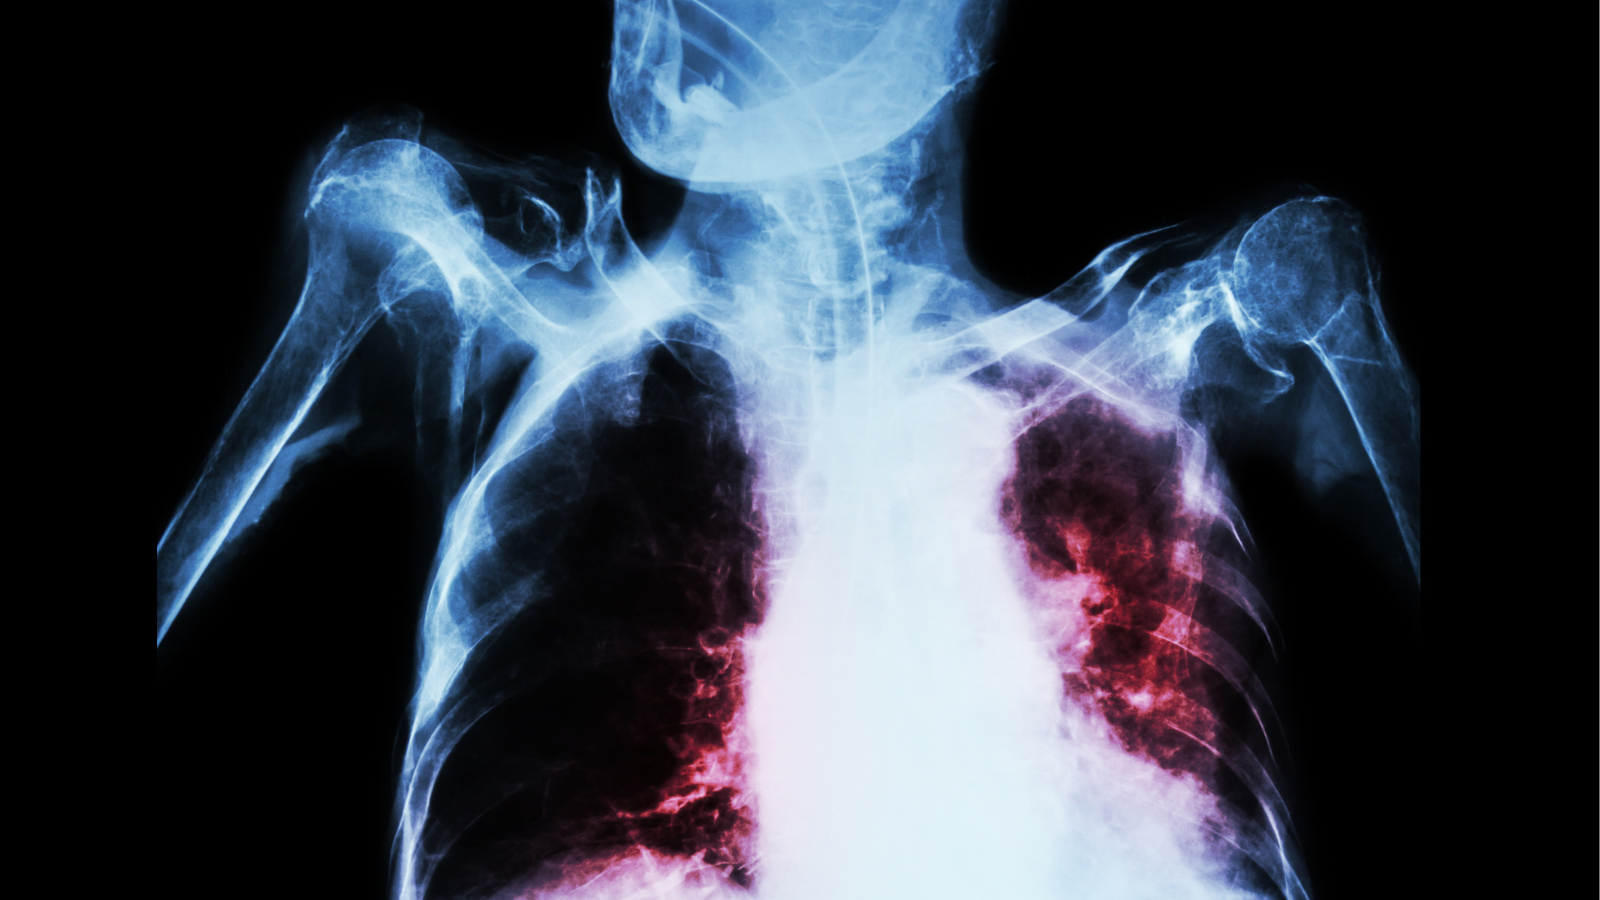

- X-quang phổi.